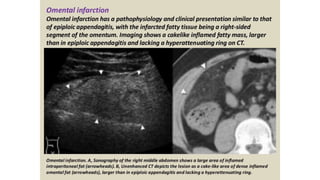

This document discusses the evaluation of right lower abdominal pain and lists appendicitis as a key cause. It notes that other potential causes include hemorrhagic cysts, heterotrophic pregnancy, salpingitis with pyosalpinx, funiculitis, and torsion of an undescended testis. The document was presented by Dr. A.S.M. Sufian of Cumilla Medical College Hospital and thanks the audience for their patience and listening.